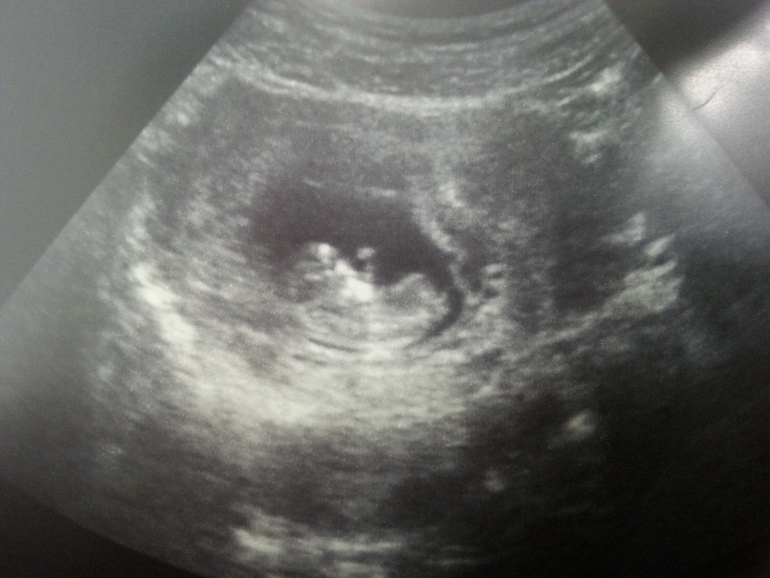

Приветик мои хорошие. Ну вот и подходит к концу 11 неделька)))

так быстро))) Самочувствие ок! уже) ходим в больницу. так надоело, уже 5 литров крови сдали с малышом) сегодня на узи были))) рассмотрела пальчики, пяточки))) мой маленький карапуз

ну и фото)

Танюш, мне кажется что у тебя девчулька. Носик такой аккуратненький и красивенький)))